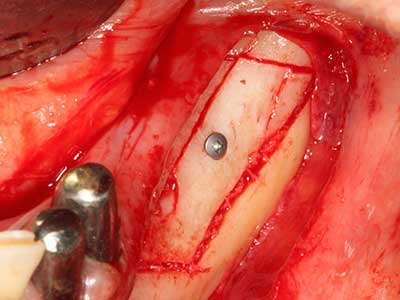

En la extracción de bloques óseos la piezocirugía también presenta ventajas adicionales: Además de la alta precisión en la osteotomía que ya se ha descrito antes, se ha comprobado que el uso de los delgados insertos de sierra resulta especialmente cuidadosas con el hueso. Frente a esto, sobre todo cuando se usan las fresas de Lindemann, cabe esperar pérdidas en la extracción significativamente más altas debido al mayor grosor de la parte frontal del cabezal (Lakshmiganthan, Gokulanathan et al. 2012). La separación basal que se necesita en particular en los injertos de bloque extraídos de forma retromolar se ve facilitada mediante sierras perpendiculares especialmente previstas a tal fin, lo que permite considerar que la cirugía piezoeléctrica es un procedimiento preciso y seguro para la obtención de bloques de hueso en el área retromolar (Happe 2007) (fig. 1-12).

Fig. 1: Preparación de una tapa ósea conforme con Piezomed (W&H, Salzburgo, Austria)

Fig. 3: La separación basal del bloque se ve facilitada con piezas dotadas de una angulación especial.